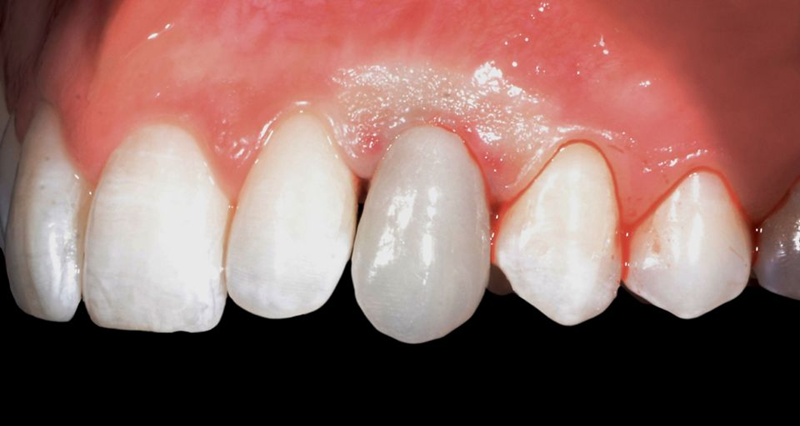

口外检查中,面部评价显示面部对称、比例匀称。微笑分析显示中线矢状面与微笑中线重合,上切牙和尖牙的暴露率为90%(图1)。微笑还显示侧切牙形状不同,与对侧恒尖牙相比,左上乳尖牙更短、更窄、颜色更黄(图2-4)。

口内检查中,乳牙处可见大量角质化牙龈,整体口腔卫生状况良好(图5-7)。

Fig. 5: Intraoral frontal view

Fig. 6: Intraoral view: The discrepancy between upper canines and lateral incisors is clear. Note that the deciduous tooth is shorter than the contralateral, both at the occlusal and at the gingival side.

Fig. 7: Magnification of the deciduous tooth: A wide amount of keratinized gingiva is shown.